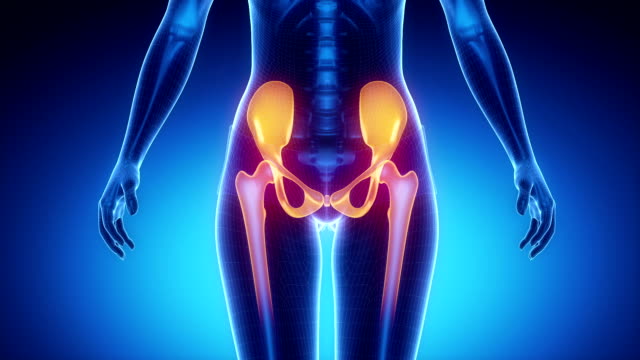

✅골반 통증 원인 추가정리

골반,고관절 통증이 발생하는 원인은 다양합니다. 위 정보에 이어서 추가적으로 알려드릴게요.

골반 통증 원인 - 근육

첫째로, 근육과 관절의 문제가 골반통증을 일으킬 수 있습니다. 골반 주변의 근육이 긴장하거나 약해지면 통증이 발생할 수 있습니다. 또한 골반 관절의 이상이나 염증도 골반통증을 유발할 수 있습니다.